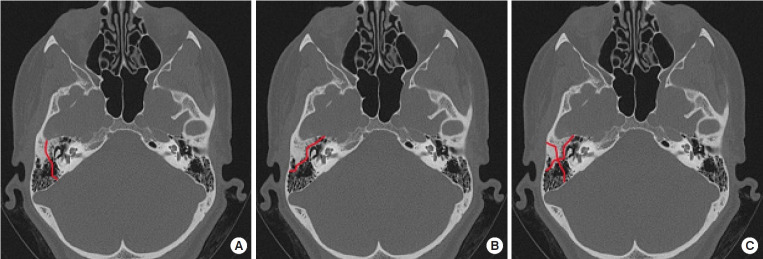

面神经刺激面部表情肌和面部副交感神经。因此,面神经麻痹会导致面部不对称、变形和功能障碍。面神经麻痹最常见的是特发性的,如贝尔麻痹,但也可能由肿瘤或外伤引起。本文将讨论外伤性面神经损伤。要确定损伤的原因,首先要确定损伤的位置。损伤的位置和程度决定了治疗方法,包括初次修复、神经移植、交叉面神经移植、神经交叉和肌肉转移。由于颞骨的复杂性,颅内近端面神经损伤给手术方法带来了挑战。这些病例的手术干预需要神经外科和耳鼻喉科的合作,而神经修复或移植是很困难的。本文介绍了周围面神经损伤的治疗方法。初次修复一般可获得最佳预后。如果在受伤后 6 个月内无法进行初次修复,则应尝试神经移植;如果超过 12 个月,则应进行功能性肌肉转移。如果当时无法使用受影响的神经,则可使用对侧面神经、同侧颌下神经或舌下神经作为供体神经。要成功治疗面神经损伤,还必须考虑其他伴随症状,如眼睑下垂或面中部下垂。

The facial nerve stimulates the muscles of facial expression and the parasympathetic nerves of the face. Consequently, facial nerve paralysis can lead to facial asymmetry, deformation, and functional impairment. Facial nerve palsy is most commonly idiopathic, as with Bell palsy, but it can also result from a tumor or trauma. In this article, we discuss traumatic facial nerve injury. To identify the cause of the injury, it is important to first determine its location. The location and extent of the damage inform the treatment method, with options including primary repair, nerve graft, cross-face nerve graft, nerve crossover, and muscle transfer. Intracranial proximal facial nerve injuries present a challenge to surgical approaches due to the complexity of the temporal bone. Surgical intervention in these cases requires a collaborative approach between neurosurgery and otolaryngology, and nerve repair or grafting is difficult. This article describes the treatment of peripheral facial nerve injury. Primary repair generally offers the best prognosis. If primary repair is not feasible within 6 months of injury, nerve grafting should be attempted, and if more than 12 months have elapsed, functional muscle transfer should be performed. If the affected nerve cannot be utilized at that time, the contralateral facial nerve, ipsilateral masseter nerve, or hypoglossal nerve can serve as the donor nerve. Other accompanying symptoms, such as lagophthalmos or midface ptosis, must also be considered for the successful treatment of facial nerve injury.